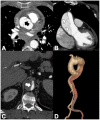

Non-traumatic thoracic aorta emergencies are associated with significant morbidity and mortality. Diseases of the intimomedial layers (aortic dissection and variants) have been grouped under the common term of acute aortic syndrome because they are life-threatening conditions clinically indistinguishable on presentation. Patients with aortic dissection may present with a wide variety of symptoms secondary to the pattern of dissection and end organ malperfusion. Other conditions may be seen in patients with acute symptoms, including ruptured and unstable thoracic aortic aneurysm, iatrogenic or infective pseudoaneurysms, aortic fistula, acute aortic thrombus/occlusive disease, and vasculitis. Imaging plays a pivotal role in the patient's management and care. In the emergency room, chest X-ray is the initial imaging test offering a screening evaluation for alternative common differential diagnoses and a preliminary assessment of the mediastinal dimensions. State-of-the-art multidetector computed tomography angiography (CTA) provides a widely available, rapid, replicable, noninvasive diagnostic imaging with sensitivity approaching 100%. It is an impressive tool in decision-making process with a deep impact on treatment including endovascular or open surgical or conservative treatment. Radiologists must be familiar with the spectrum of these entities to help triage patients appropriately and efficiently. Understanding the imaging findings and proper measurement techniques allow the radiologist to suggest the most appropriate next management step.